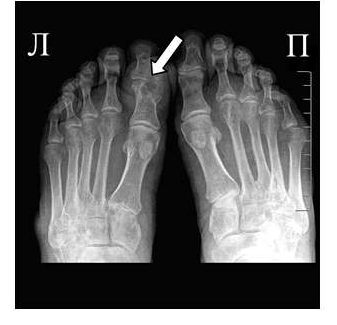

Наиболее часто, процесс начинается в 1 пальце стопы (головка плюсневой кости и основание основной фаланги), в дальнейшем могут поражаться и другие отделы. Происходит отложение мочекислых солей внутри сустава, в связках и суставных элементах, обычно в местах прикрепления суставной капсулы.

Клиника острого подагрического артрита характеризуется сильными болями в области пораженного сустава, кожа над суставом отечна, гиперемирована, напряжена. Повышено содержание мочевой кислоты в крови (в норме 0,35 ммоль/л) и выделение мочевой кислоты с мочой — гиперурикозурия (в норме колеблется в пределах 2,9—5,9 ммоль). Могут определяться тофусы, в частности в ушных раковинах, иногда они сопровождаются изъязвлением с выделением крошковидной массы. Рентгенологически — чаще в типичном месте отмечается вздутие эпифизарного отдела с кистоподобной перестройкой костной структуры, с истончением кортикального слоя. В случаях нарушения целостности кортикального слоя образуются краевые узуры с ровными, четкими контурами, окруженные ободочком склероза, размером 5—6 и даже 9 мм. Суставная щель представляется суженной. Даже при значительных деструктивных изменениях наблюдается лишь нерезко выраженный остеопороз в прилежащих отделах костей. В далеко зашедших случаях в проекции костно-мозгового канала могут отмечаться множественные мелкие плотные включения без четких контуров, создающие «мраморность» костной структуры. Эти включения

обусловлены мочекислыми солями. Могут наблюдаться также анкилозы, подвывихи и беспорядочное смещение пальцев в разные стороны. В ряде случаев приходится проводить дифференциальный диагноз между ревматоидным полиартритом и подагрой.